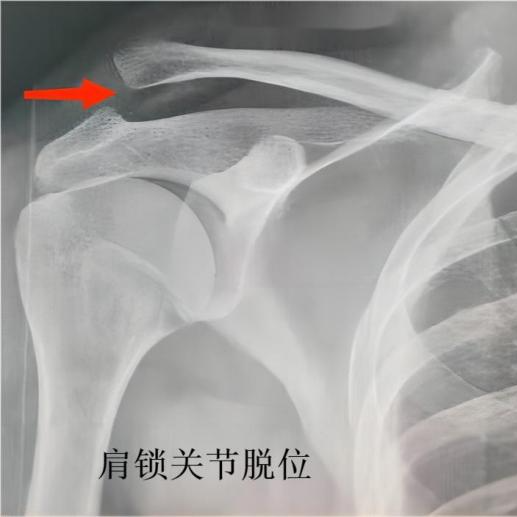

同样是肩膀“掉环”,检查结果却大相径庭——小王是肩关节脱位,陈叔则是肩锁关节脱位。这两种损伤是肩部外伤中常见的类型,尤其在急诊创伤患者中占比颇高。肩关节脱位约占全身关节脱位的45%,是临床最常见的关节脱位类型,高发于20-40岁青壮年男性,多与运动损伤、意外摔倒相关。而肩锁关节脱位占肩部损伤的12%—15%,高发人群分为两类:20-30岁的运动爱好者(篮球、橄榄球、柔道等对抗性运动)和40-60岁的中老年人群(意外摔倒、交通事故)。

肩锁关节则是位于肩膀外侧最顶端,是锁骨外侧端与肩胛骨肩峰的连接部位,靠肩锁韧带(浅层稳定)和喙锁韧带(深层稳定)固定,如同“两个积木靠绳子绑在一起”。肩锁关节脱位的损伤机制以直接暴力为主——肩部外侧直接撞击或着地(如陈叔骑车摔倒的场景),外力使锁骨末端与肩峰分离,韧带被拉伤或断裂;间接暴力(如手臂牵拉)导致的脱位仅占10%左右。

肩关节脱位表现为肩膀“方肩畸形”(正常圆润轮廓消失),触摸关节盂处会感觉“空虚”,肱骨头可能在肩前方摸到;肩锁关节脱位表现为肩膀顶端凸起(“硬疙瘩”或“小山包”),肿胀集中在锁骨末端与肩峰连接处。

肩关节脱位可能伴随腋神经损伤(肩部皮肤感觉减退)、肩袖撕裂;肩锁关节脱位重度患者可能出现锁骨末端明显移位上翘,按压时可触及“琴键征”(锁骨远端可被按下去松手后自动回弹起来)。

首选检查,可清晰显示肱骨头是否脱位、肩锁关节是否错位及程度。肩关节脱位X光片可见肱骨头位于关节盂前方/下方;肩锁关节脱位可通过“肩锁关节间隙”判断。